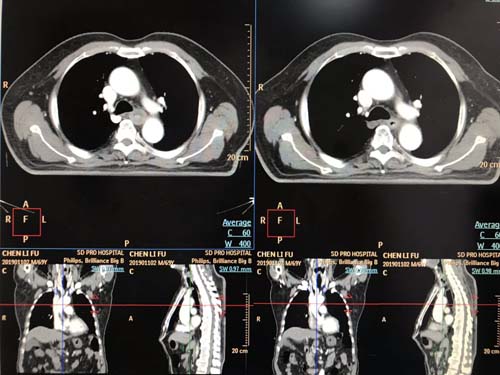

像这样成功的病例并非个例,山东省立医院肿瘤治疗中心依托自身雄厚的医资力量,发挥先进医疗资源优势,运用国际国内前沿诊疗方法,结合具体病情,量体裁衣,为每名患者制定个体化治疗方案。科室拥有国际先进的飞利浦16排大孔径CT模拟定位机PHILIPS Brilliance Big Bore CT和GE/美国Discovery RT临床版全视野诊断级大孔径 CT,是目前国际最先进的大孔径CT模拟机。先进的4D-CT定位功能,配合个体化治疗计划,实现真正、完整的4D-CT模拟,能够快捷的为肿瘤放疗患者进行精准的定位,同时也减少了由于患者呼吸、心跳带来的剂量误差,在增加肿瘤治疗疗效的同时,降低正常组织的不良反应,让放疗摆位更准确,剂量误差更小,使放疗技术水平又上了一个新的台阶。